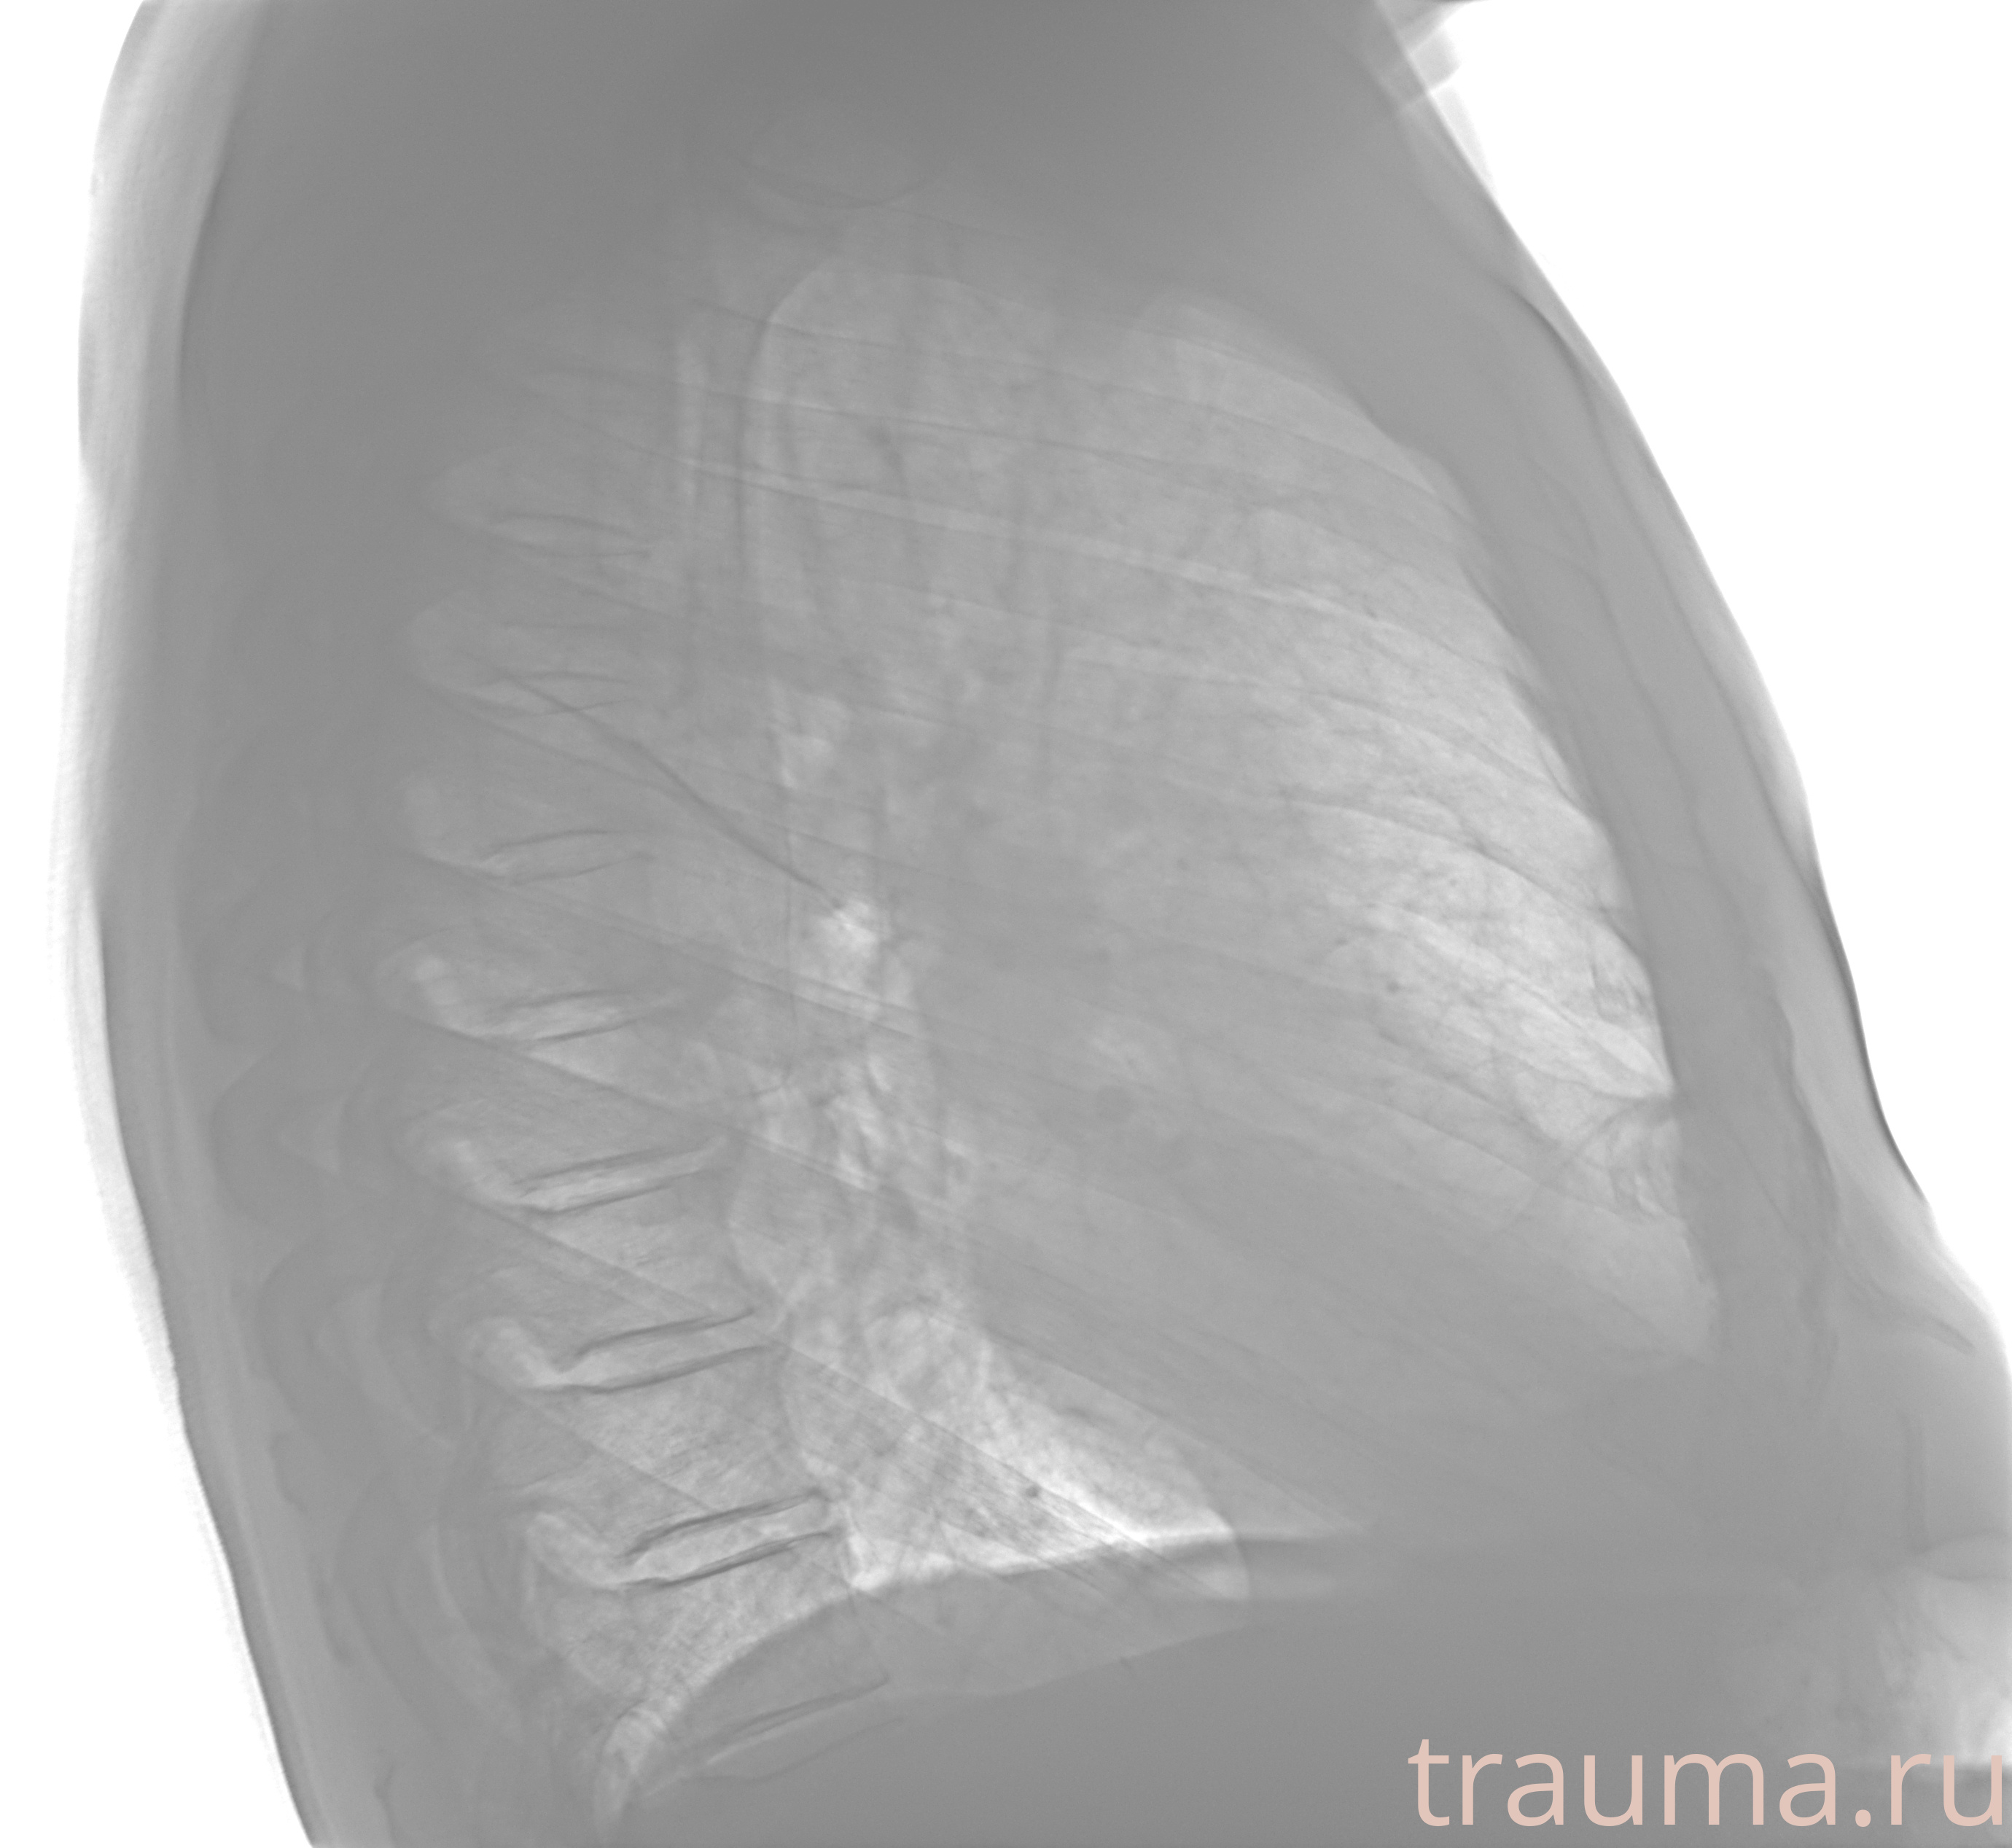

Рентгенограммы

Рентген на дому: по вашему адресу приезжает врач-рентгенолог, травматолог-ортопед с мобильным рентгеновским аппаратом, проводит диагностику травмы или заболевания, делает необходимые рентгенограммы, дает рекомендации по дальнейшему лечению. Получить качественные снимки в домашних условиях возможно благодаря уникальной методике, разработанной МосРентген Центром для института  Склифосовского

Яркость: 1   Контраст: 1   Инвертировать: 0 Увеличение: 1

Перетаскивайте мышь вверх/вниз для контраста, влево/право для яркости. Прокрутка колесом изменяет масштаб. Нажмите Сбросить для возврата к исходному изображению. При увеличении держите мышь в той области, которую хотите рассмотреть.